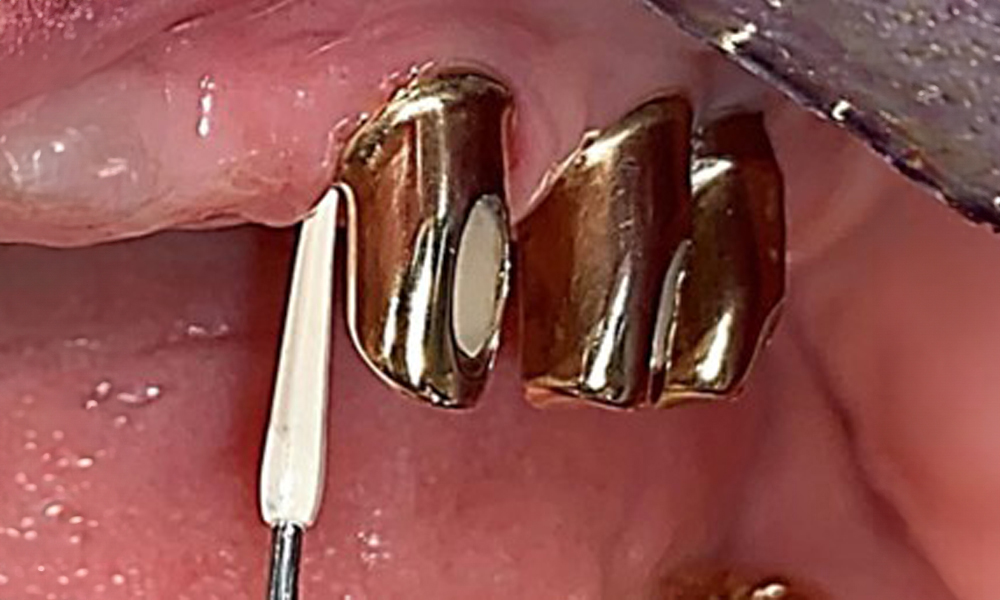

The intraoral mucosa must be examined for possible fungal infections and pressure spots. The dentures must be visually inspected for cleanliness. The present case presented with interdental discolouration, attributed to tea consumption (Fig. 7). The dentures should be professionally cleaned in the dental practice using disinfection and cleaning baths.

The patient was fitted with a combined removable maxillary telescopic prosthesis more than 25 years ago (Fig. 1, Fig. 2, Fig. 3) and is very happy with her dentures. The patient has an adequate fixed denture for the mandible (Fig. 4).

The dental findings are as follows: Combined removable implant and tooth-supported telescopic prostheses on implants 15, 13, 21, 23, 24, 25 and tooth 11 (Fig. 1, Fig. 2, Fig. 3). The patient was fitted with a fixed mandibular denture. Adequate bridges were present over 37 to 34 and 45 to 47 (Fig. 4), the crown margins were intact and there were no active caries. A composite filling with a marginal gap was present on tooth 43. There was mandibular gingival recession, exposing 1 to 3 mm of root surface. This also applies to 11.